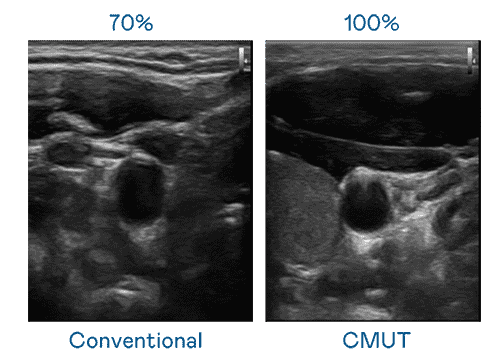

CMUT 技术是一种用电容式微机电元件来产生超音波讯号的技术。。。与传统 PZT 压电式技术相比,,CMUT 频宽增加 30%,,更宽频的超音波讯号让影像解析度大幅提升,,是实现高影像品质医疗超音波扫描、、促进精准医疗发展的关键技术。。。

超音波影像的解析度高低,,,首先取决于探头能发出的讯号频宽。。。。人生就是博 CMUT 可提供高清晰的超音波讯号,,,提供高频宽、、、、高灵敏度、、、、影像纹理细节更高的超音波影像,,协助医护人员缩短影像判读时间及利用精准的医疗影像进行诊断。。